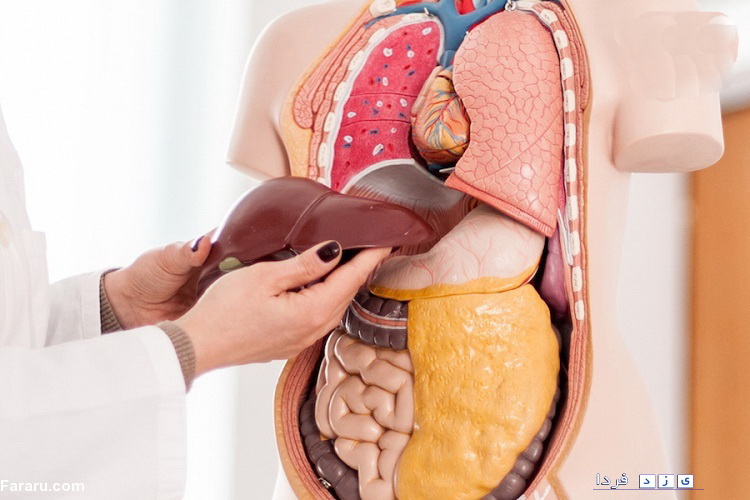

کبد دومین عضو بزرگ در بدن است. وظیفه کبد هضم تمامی مواد غذایی است که مصرف میکنیم و مینوشیم.

در صورتی که مقدار چربی انباشته شده در کبد بسیار زیاد شود، ممکن است به کبد آسیب برساند. زمانی که سلولهای قدیمی آسیب دیده باشند، کبد معمولا خودش را با ساخت سلولهای جدید کبدی ترمیم میکند. زمانی که این آسیبها به طور پیوسته تکرار شوند، زخمهای دائمی ایجاد میشوند، که به آن "سیروز کبد" میگویند.